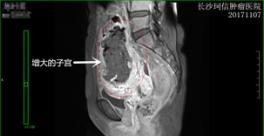

圖爲龍女(nǚ)士治療前與治療後對比照(zhào)

長沙珂信腫瘤醫院婦瘤科(kē)一病區主任張建飛介紹,龍女(nǚ)士剛到院時,病情危重,合并重度貧血,感染,子宮增大(dà)如(rú)孕5個月大(dà)小,入院後反複高熱、腹痛,腸梗阻,“随時可(kě)能出現子宮穿孔,大(dà)出血,腫瘤腦轉移,肺轉移”,積極給予抗炎,糾正貧血,及對症支持治療。因病情危重,預後評分(fēn)屬于高危組,故化療方案選用的聯合化療——EMA-CO方案。”